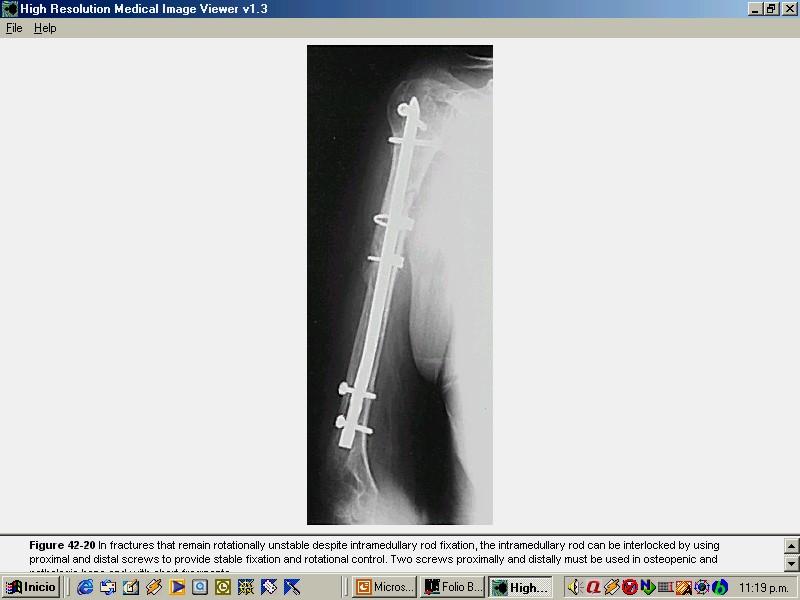

CLAVADO INTRAMEDULAR DESDE LA DIAFISIS

FRACTURAS 1/3 PROX DE HUMEROFRACTURAS 1/3 PROX DE HUMERO ENCLAVADO ENDOMEDULAR RETROGRADO. ENCLAVADO ENDOMEDULAR RETROGRADO. ENCLAVADO ENDOMEDULAR FLEXIBLE. Tipo Ender. ENCLAVADO ENDOMEDULAR FLEXIBLE. Tipo Ender.